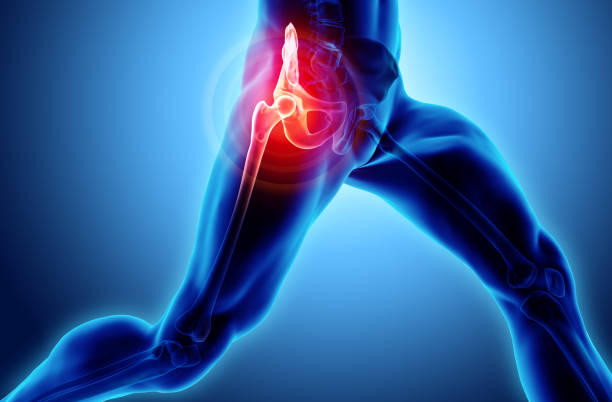

골반 통증에 좋은 운동 - 엉덩이 근육을 강화하는 운동

엉덩이 근육을 강화하는 운동은 골반 통증을 완화하는데 중요합니다. 대둔근이라고 불리는 엉덩이 근육을 강화하기 위해 다리를 뒤로 들거나 런지 운동을 실시하세요. 양쪽 다리를 균형 있게 강화하도록 노력하세요.